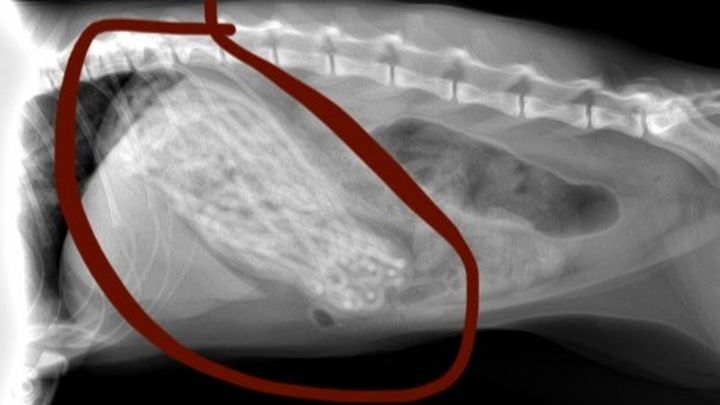

Recently, I noticed that Luna had been eating far less and vomiting for the past week and a half or so, but I was alarmed today (January 5, 2022) when I saw that she had vomited up half of a hair tie. Naturally, I immediately took her to the vet where they did a body exam and some scans. When they showed me the X-Rays (attached in photos), my heart immediately dropped. Luna's stomach was completely filled with black hair ties - the vet expressed that her stomach was so expanded that it would be surprising to him if she could fit anything else in there.

Luna requires an emergency surgery operation (gastrostomy) which they will be performing tomorrow (January 6th, 2022) where they will be opening her stomach to empty the contents and remove the hair ties that are stuck in her stomach. Luckily, the vet told me that these operations are relatively low risk, but her case is unusual in the extent to which her stomach is full, and complications are always possible. Assuming the operation goes well, they will keep her for another two days in the facility to monitor her and ensure she is recovering well.